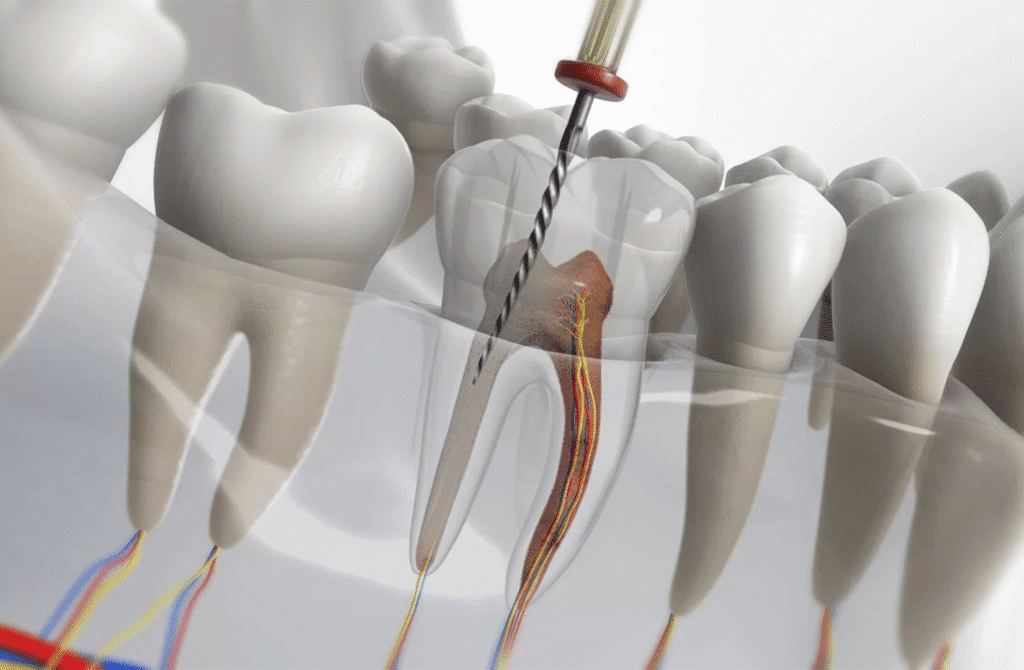

Endodoncia

Alivie el dolor y preserve su sonrisa con nuestros tratamientos de

conducto, realizados por expertos en Endodoncia.

Realice su tratamiento de nervio con un Especialista

Tratamiento de Nervio